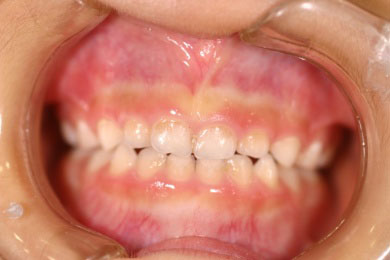

乳歯の反対咬合(下顎前突)を矯正して正常な上下関係に矯正した症例

Before

After

日本橋りゅうデンタルクリニックの子供の矯正歯科治療例です。子供の場合、なるべく早い時期に不正咬合を見つけて矯正歯科治療を開始してあげるべきです。このことによって、顎顔面の成長発育が正常に行われていきます。

年齢 5歳

治療期間 8ヶ月

治療費用 600,000円

治療のリスク 患者様が装置を使用しないと治りません